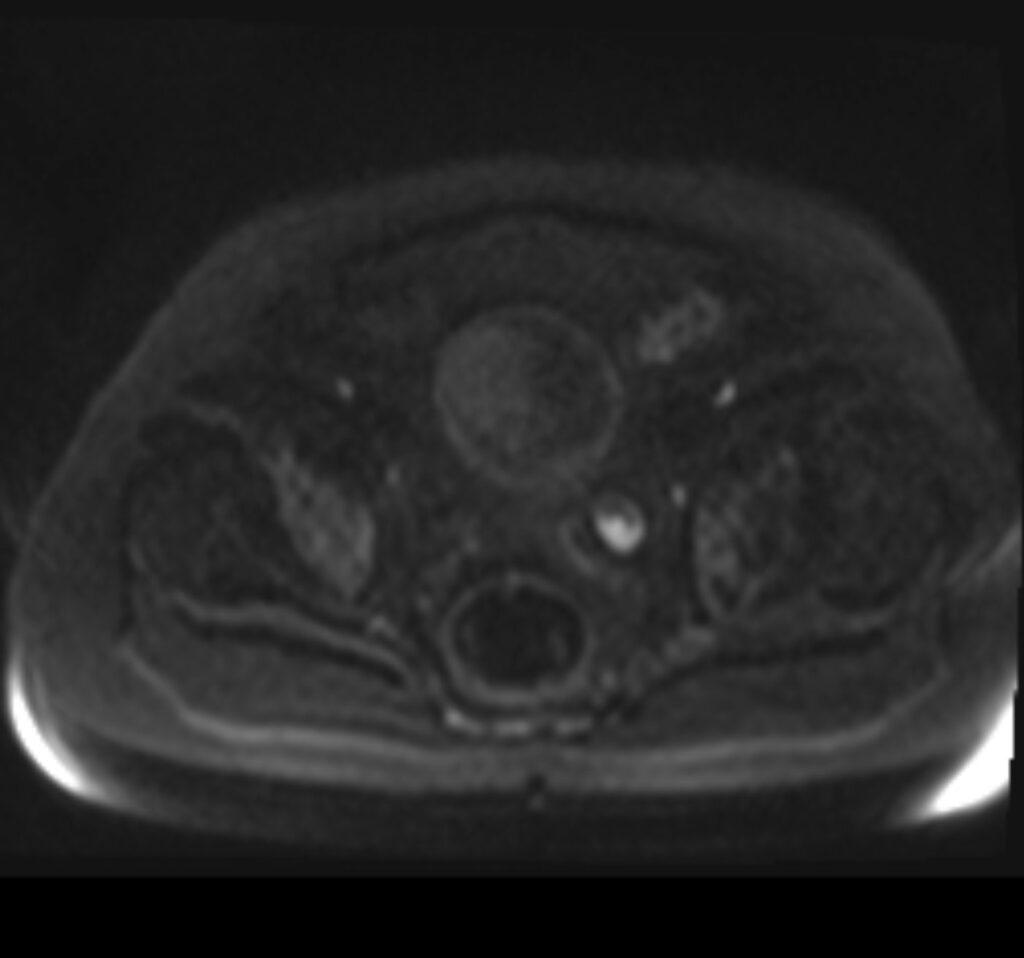

MR images revealed the left dilated ureter and intraluminal polypoidal masses at its distal segment. Associated moderate left hydronephrosis is noted.